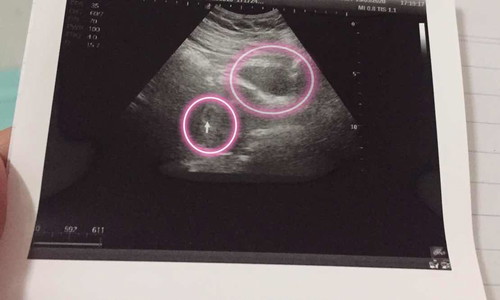

แบบนี้ตั้งครรภ์ แน่นอน ใช่มั้ยคะ แล้วสองถุงนี้ต่างกันยังไงคะ

2ถุงคือเเฝดคนละใบค่ะ หน้าเค้าจะไม่เหมือนกัน เหมือนพี่น้องทั้วไปบางคนอาจจะเป็นญ.ช ญ.ญ ช.ช เเต่ถ้าถุงเดียวกันหน้าเค้าจะคล้ายๆกันเค้าจะมีเพศเดียวกันประมานนี้ค่ะแม่

น้องแฝด